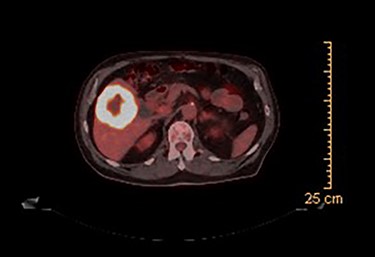

CT guided biopsy of the lesion demonstrated the presence of invasive squamous cell carcinoma with p40-positive and focally positive for CK7 cells. Caris testing was positive for PDL1 (95%) with stable MMR and low TMB. PET scan revealed a large hypermetabolic, centrally necrotic mass involving liver segments V, VI without any abnormal FDG uptake within the head, neck or chest. Pertinent images from the PET scan are demonstrated in Figs 1 and 2.

PET scan (axial view): hypermetabolic, centrally necrotic mass involving liver segment V, VI.